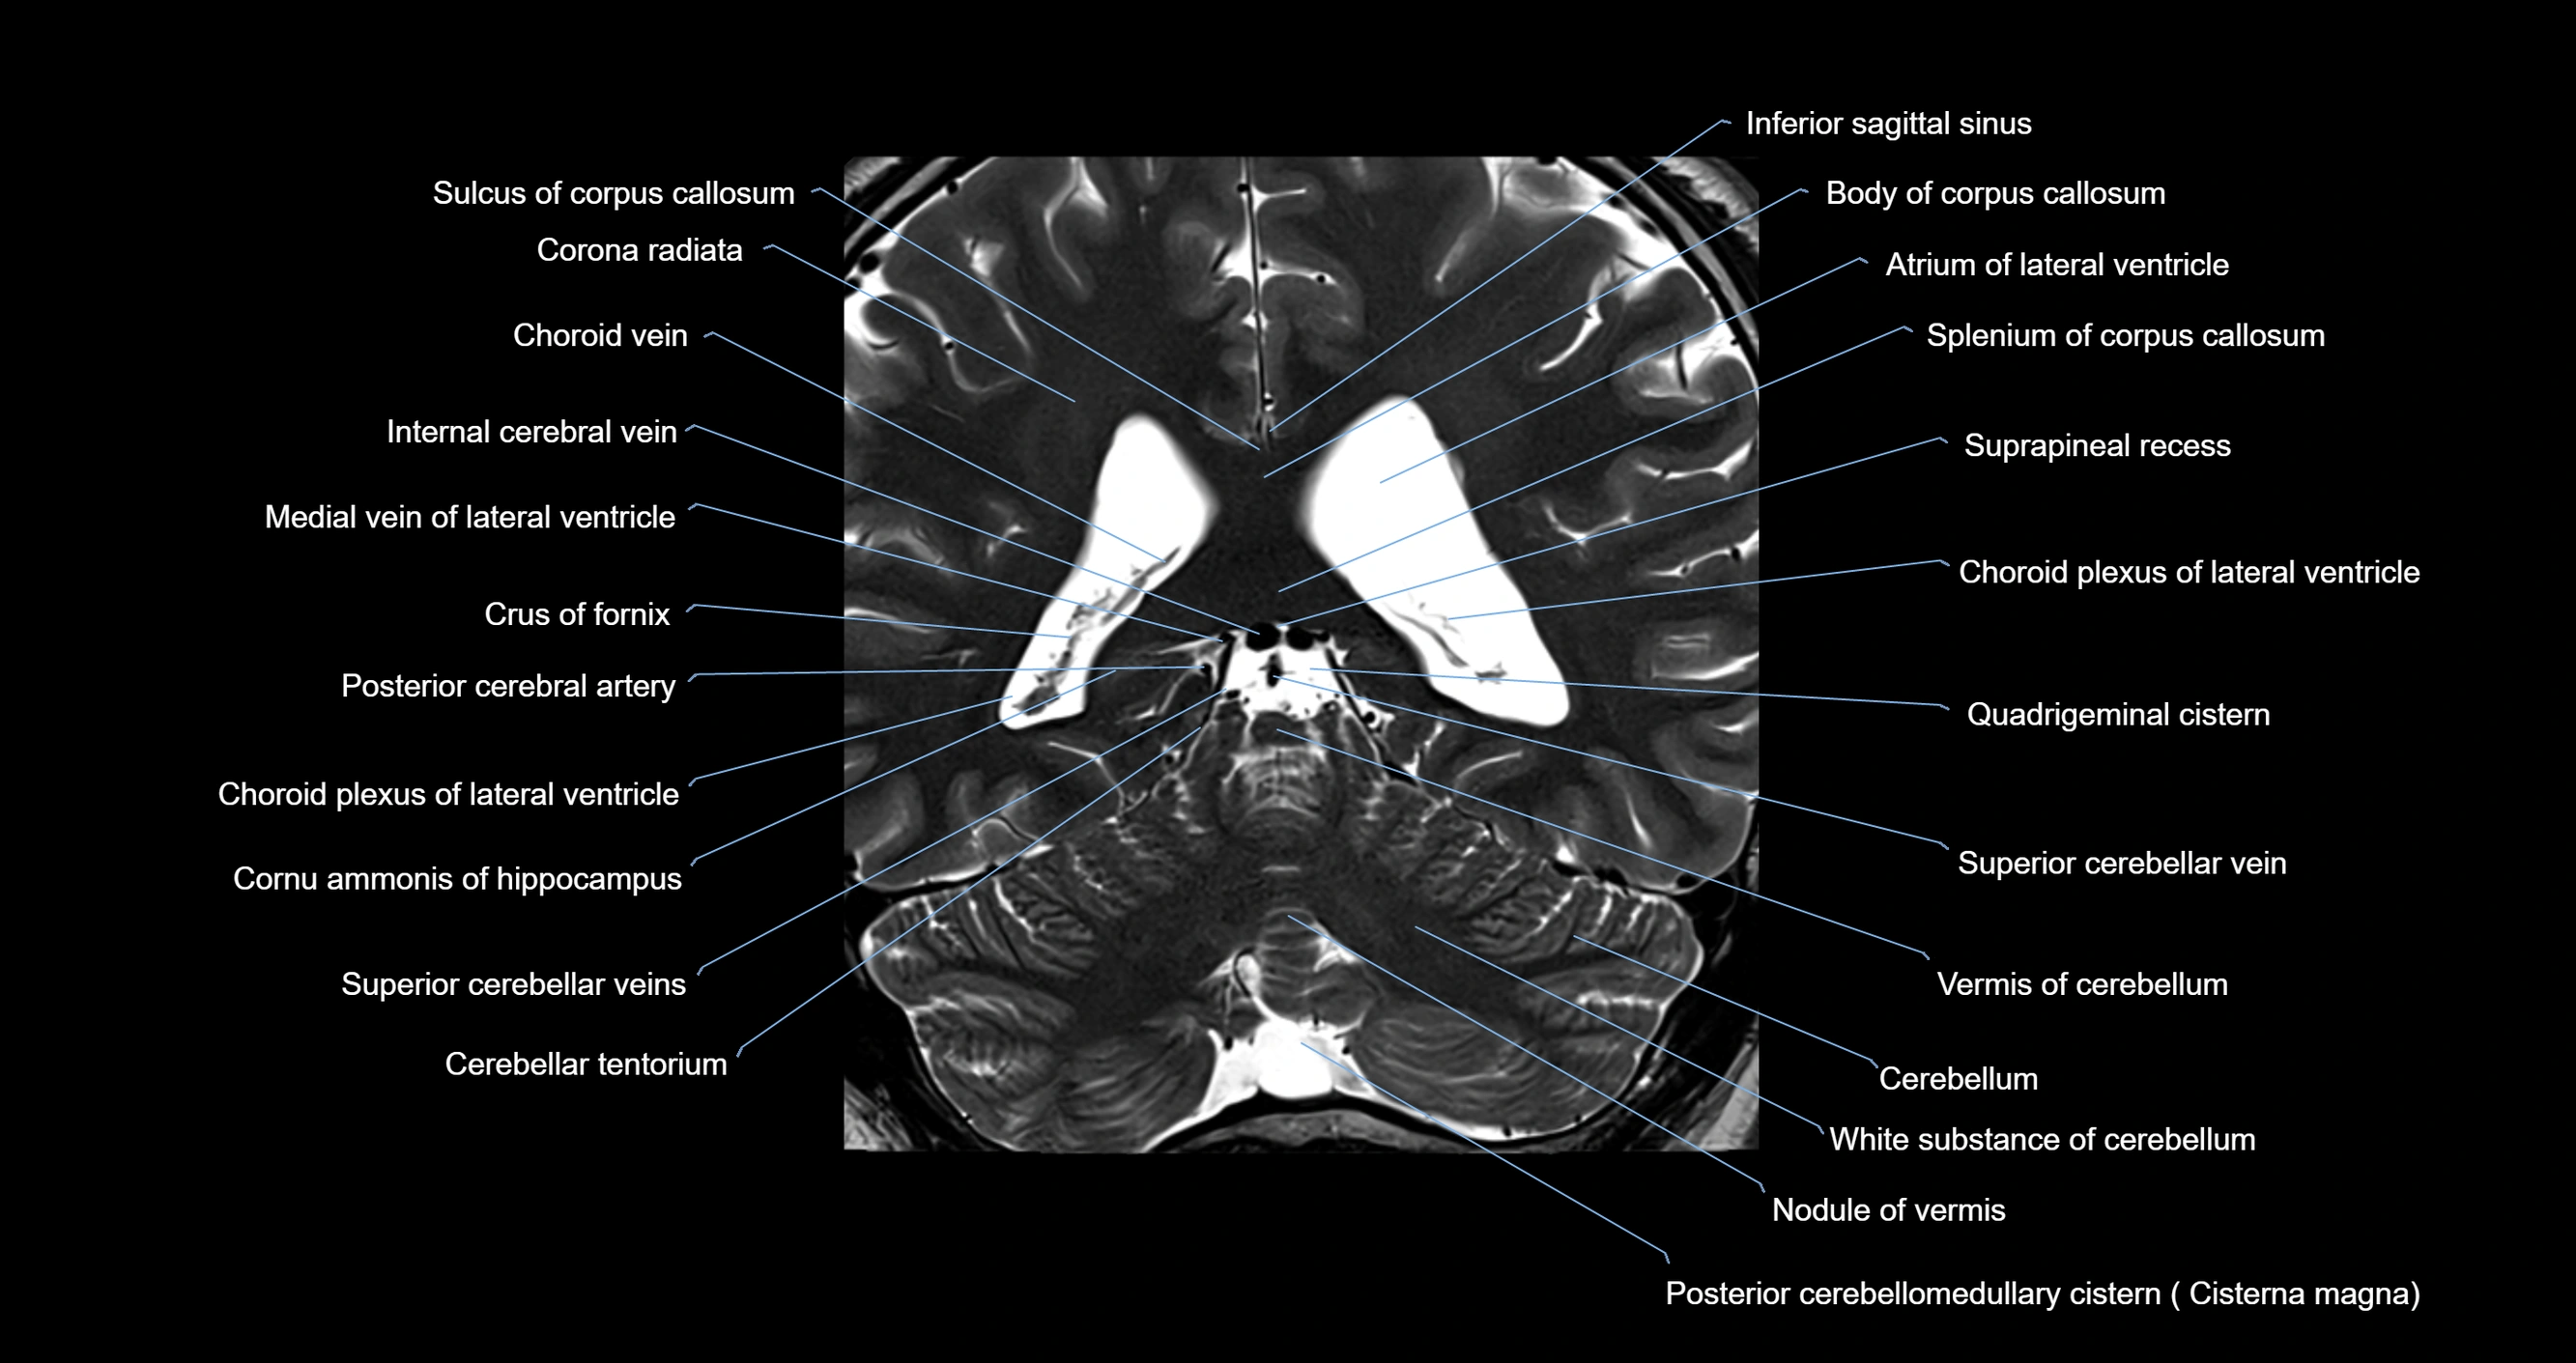

- Atrium of lateral ventricle

- Body of corpus callosum

- Body of fornix

- Body of lateral ventricle

- Cerebellum

- Choroid plexus of the lateral ventricle

- Cisterna magna

- Corona radiata

- Crus of fornix

- Inferior sagittal sinus

- Internal cerebral vein

- Medial vein of lateral ventricle

- Nodule of vermis

- Posterior cerebellomedullary cistern (cisterna magna)

- Posterior cerebral artery

- Quadrigeminal cistern

- Splenium of corpus callosum

- Superior cerebellar vein

- Suprapineal recess

- Vermis of cerebellum

- White substance of cerebellum